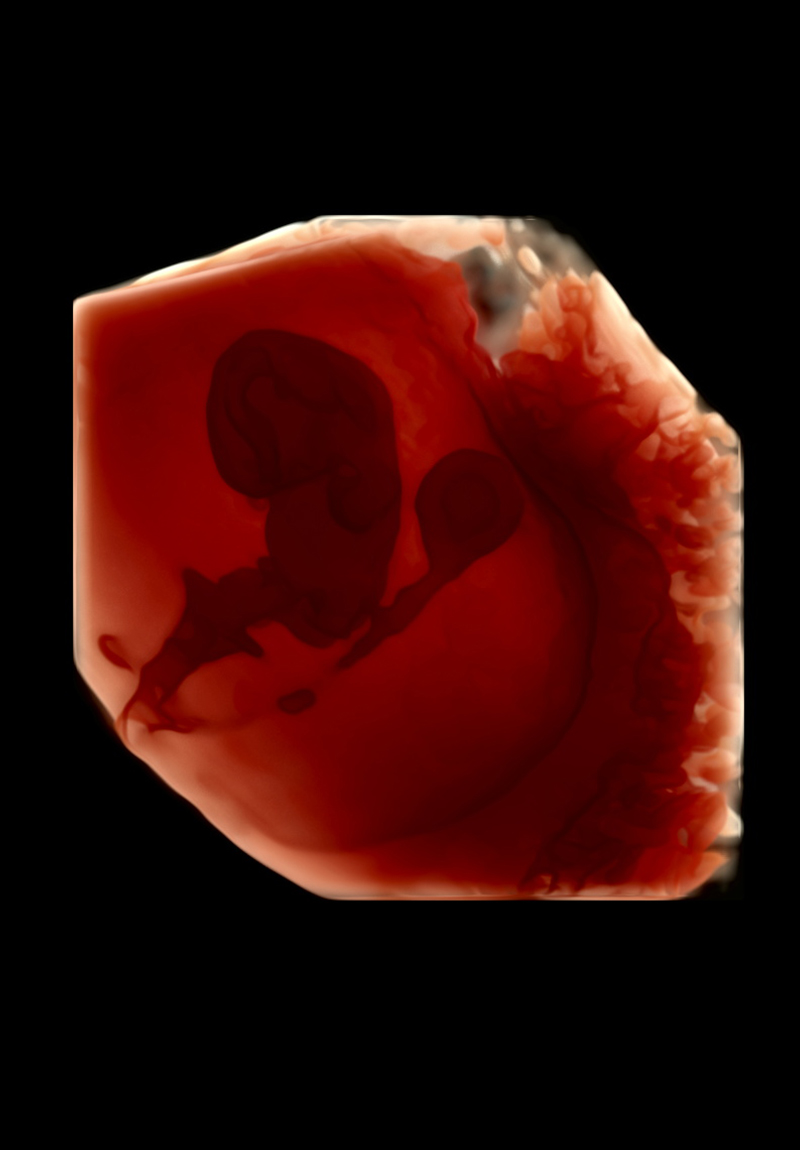

Eco Anatómico 4D

Realizado entre las semanas 20 y 30, el Eco Anatómico 4D, es un estudio que permite una valoración detallada del crecimiento, órganos y estructuras de bebé. Este eco es crucial para la detección temprana de malformaciones congénitas. Si la posición de bebé y las condiciones nos permiten, podemos llevarnos un hermoso recuerdo al tomar fotografías en 4d.